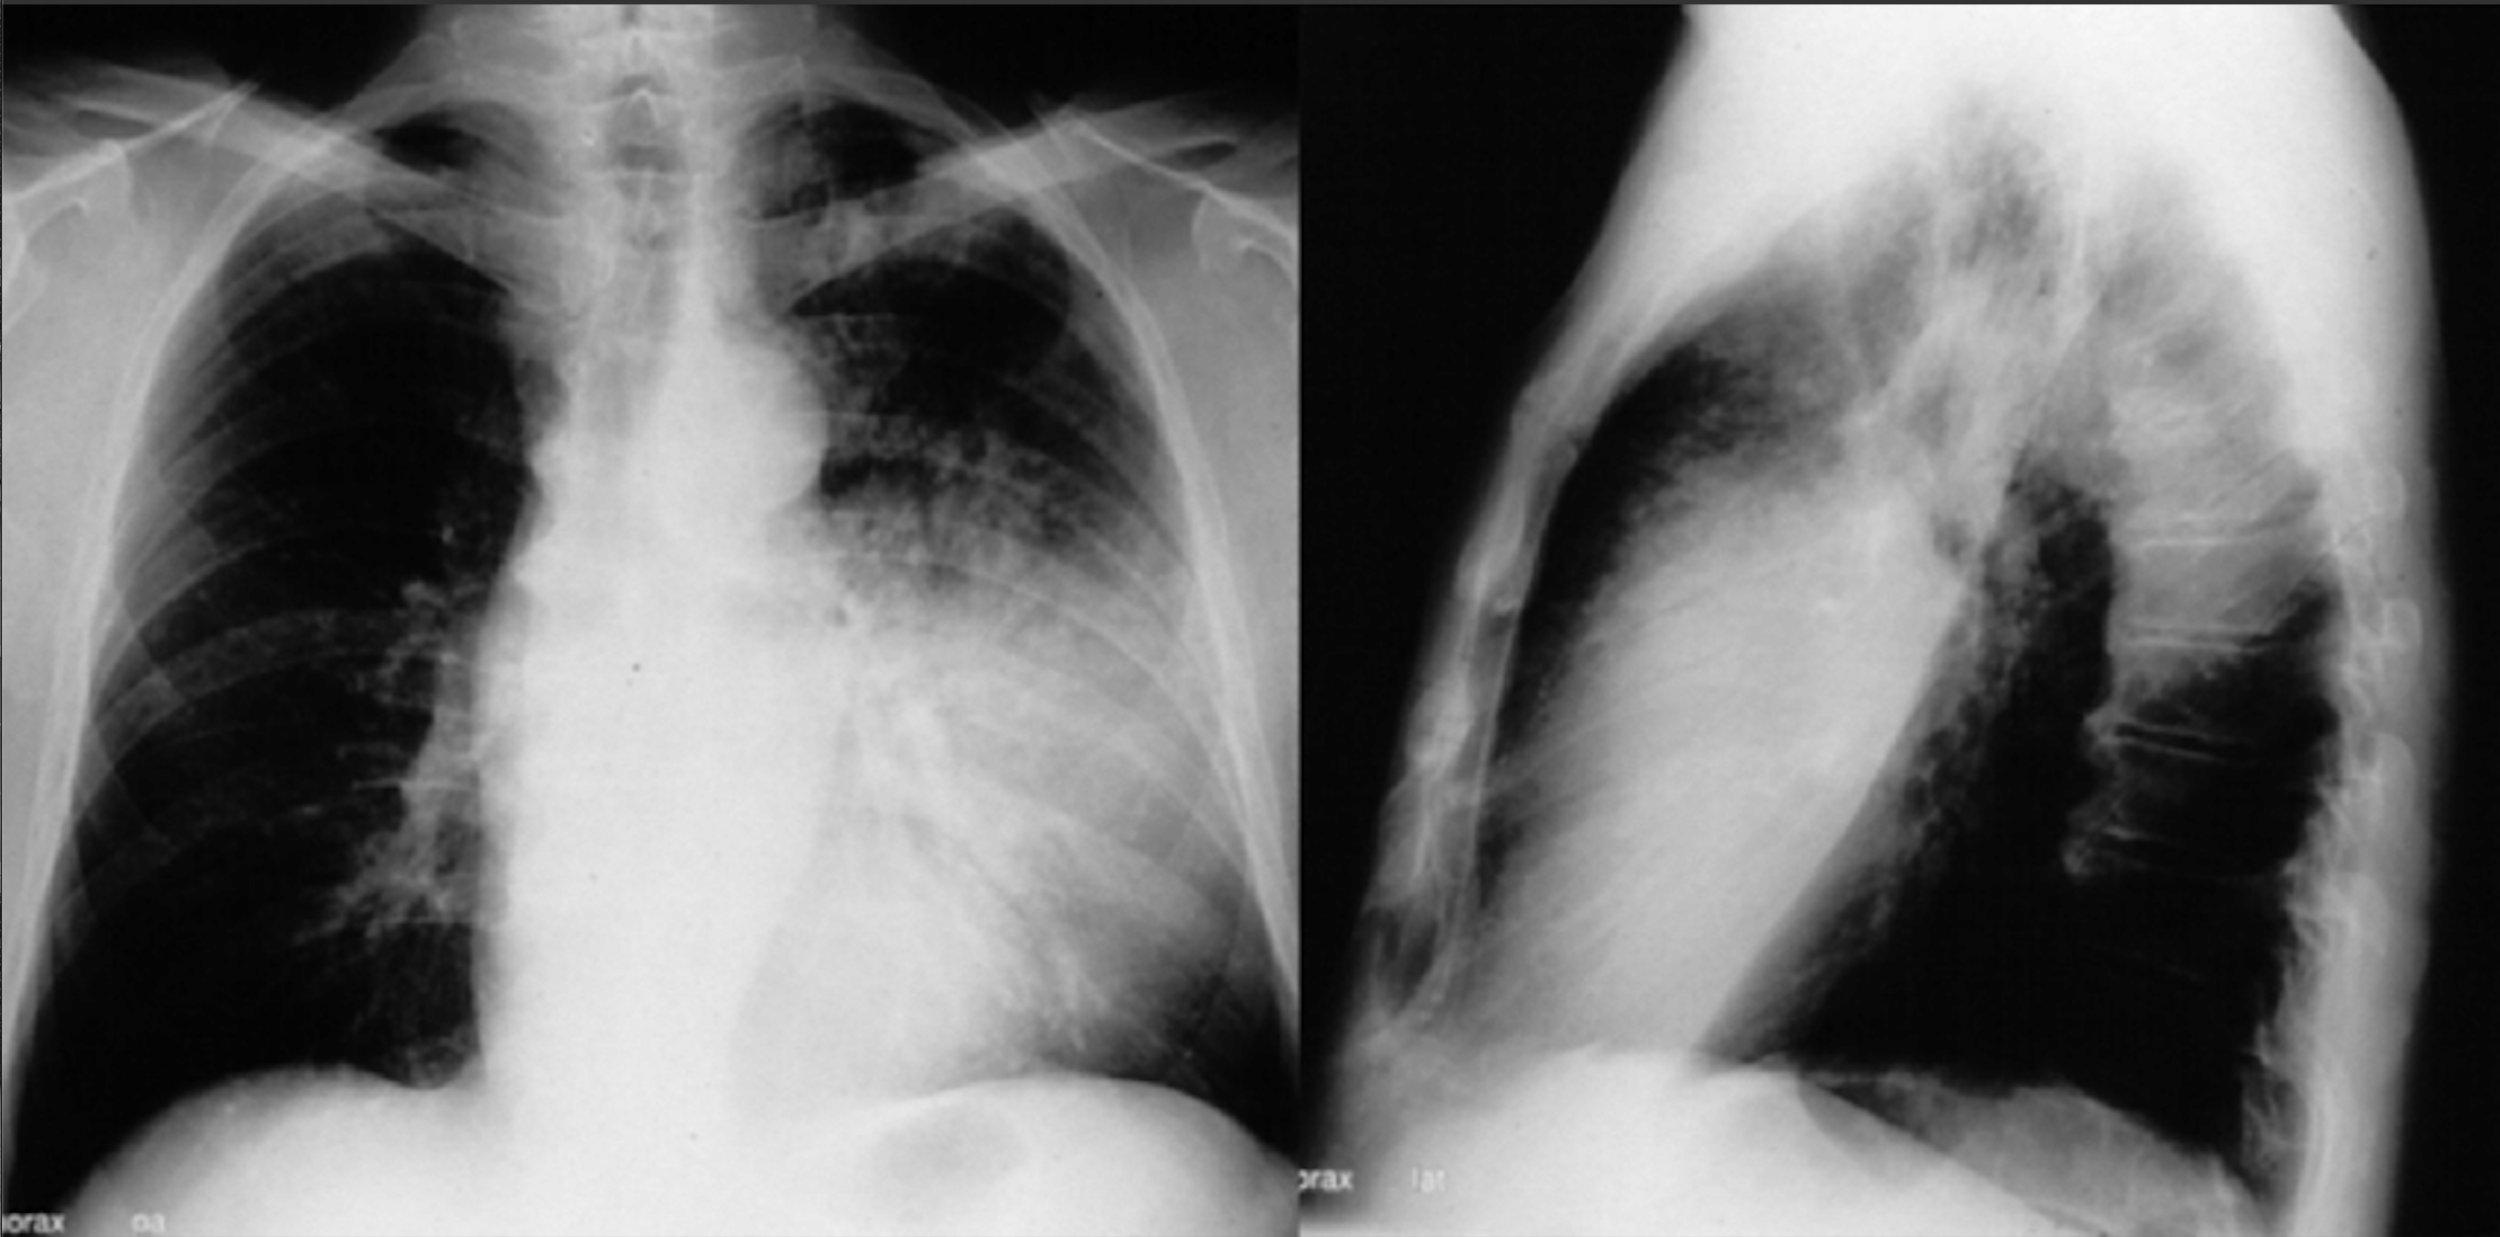

Pneumonia

But where?